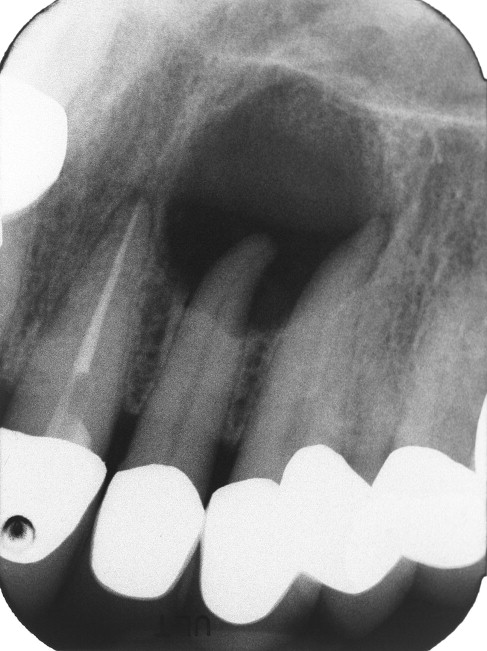

방사선 사진 검사도 중요한 이유

엑스레이 검사도 필수입니다. 위 엑스레이 사진을 보시면 치아의 뿌리 끝부분에 검정색 동그라미 부분이 있는걸 아실 수 있죠. 이게 원래는 다 뼈로 차있어야 하는 공간입니다. 주변을 보시면 하얗게 뼈가 있죠. 그 부분만 검정색이라는건 뼈가 없다는 겁니다. 왜 뼈가 없어졌을까요? 대신 그 자리에 염증이 생겼다는 뜻입니다. 이런 식으로 보인다면 이건 100% 신경이 감염된걸로 볼 수 있습니다. 이미 감염이 되어 뼈까지 녹일정도로 심하다는 겁니다. (출처: https://www.sciencedirect.com)

신경치료 전에 방사선 사진 검사도 거의 반드시 진행됩니다.

이 검사를 통해

치근단 염증 여부

뿌리 형태

근관 개수

주변 뼈 상태

를 확인할 수 있습니다.

치과 방사선 영상은

진단과 치료 계획을 세우는 데 핵심 도구로 알려져 있습니다.

또한 치료 전 촬영한 영상은

치료 후 회복 상태를 확인하는 기준이 되기도 합니다.

신경치료 전 방사선 검사는 치료 계획의 중요한 기준이 됩니다